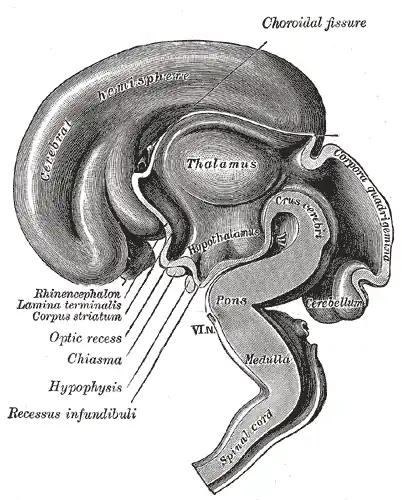

El hipotálamo[1] es una región del cerebro anterior, que forma parte del prosencéfalo secundario embrionario y en el adulto se encuentra situada debajo del tálamo.[2] Produce diferentes hormonas, entre ellas hormona antidiurética y oxitocina, también secreta varios neuropéptidos llamados factores hipotalámicos que actúan sobre la adenohipófisis y regulan su producción hormonal. Otras funciones del hipotálamo son mantener la temperatura corporal, e influir en diferentes conductas, entre ellas las relacionadas con: la alimentación, ingesta de líquidos, apareamiento y agresión. Es el regulador central de varias funciones viscerales autónomas y endocrinas y además actúa como punto de relevo en la información que partiendo del cerebro alcanza la médula espinal.[3][4]

El hipotálamo humano es el sector del encéfalo que ocupa un volumen de cuatro centímetros cúbicos, el 0.3 % del volumen encefálico normal de un adulto, y pesa entre 5-8 gramos.[5][6] Ocupa la porción más ventral del diencéfalo y forma la parte anterior de las paredes laterales y del piso del tercer ventrículo.[5] Se localiza por debajo del tálamo y es una parte importante del sistema límbico. Sus puntos de referencia externos son el quiasma óptico, el tuber cinereum y los cuerpos mamilares.[7] Está unido al lóbulo posterior de hipófisis por el tallo hipofisario o infundíbulo.[8]

En la morfogénesis, el suelo del hipotálamo forma el infundíbulo, una evaginación digitiforme y hueca, a partir de la que se desarrollan dos estructuras: la neurohipófisis y la eminencia media. Esta última es una zona de contacto neurohemático, que forma una interfaz funcional entre el hipotálamo y el lóbulo anterior de la hipófisis.[5]